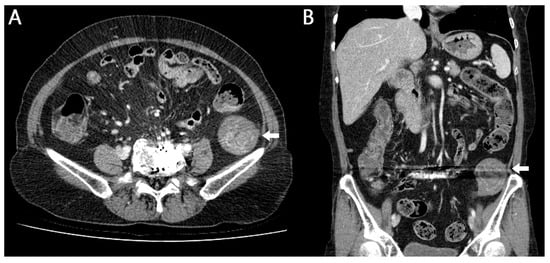

Figure 1. Retention of gauze, sponges, or various surgical instruments after surgery is rare []. Although this complication is entirely preventable, when it does occur, it may lead to severe, potentially life-threatening consequences. Nevertheless, the true incidence is likely underreported because of medicolegal concerns []. Gossypiboma, a term combining gossypium (Latin for cotton) and boma (Swahili for “to hide”), refers specifically to retained surgical textiles []. Gossypiboma is an uncommon yet significant postoperative complication resulting from retained surgical materials. Despite its rarity, it can present with a wide range of clinical manifestations and may lead to substantial morbidity. Its incidence, clinical features, and preventive strategies have been extensively discussed in the literature. Here, we report a case of gossypiboma discovered on abdominal computed tomography (CT) in a patient who presented to our hospital with abdominal pain. The diagnosis was confirmed following surgical resection of the abdominal mass. A 61-year-old female patient visited our hospital complaining of pain in the left lower abdomen that began 3 days ago. The patient said that she had a history of lumbar disc surgery at another hospital 10 years ago and the surgery was performed on the lower left abdomen. The patient had undergone lumbar disc surgery at another hospital, and although the exact surgical approach was not documented, the procedure was presumed to have been performed via a retroperitoneal approach based on imaging findings and the operative scar location. In addition, there was a history of coil embolization for subarachnoid hemorrhage 4 years ago. The physical examination revealed blood pressure 120/70 mmHg, pulse rate 68/min, respiration rate 20/min, and body temperature 36.5 °C and the patient showed acute illness. On abdominal examination, a relatively immobile mass without tenderness was palpable in the left pelvic region. Peripheral blood test showed white blood cell 6390/mm3 (Neutrophil 60.9%), hemoglobin 12.3 g/dL, and platelet 205,000/mm3. Biochemistry analysis showed aspartate aminotransferase (AST)/alanine aminotransferase (ALT) 17/12 IU/L, total/direct bilirubin 0.5/0.2 mg/dL, blood urea nitrogen 18 mg/dL, creatinine 0.5 mg/dL, and C-reactive protein (CRP) 0.5 mg/dL. Abdominal CT image: (A) axial and (B) coronal CT images demonstrate metal artifacts from previous lumbar disc surgery and an ovoid 4.5 × 4.7 × 6.1 cm sized poorly enhancing low-attenuation lesion with inner whirled high-attenuation portions in retroperitoneal space of left upper pelvic cavity (arrow).